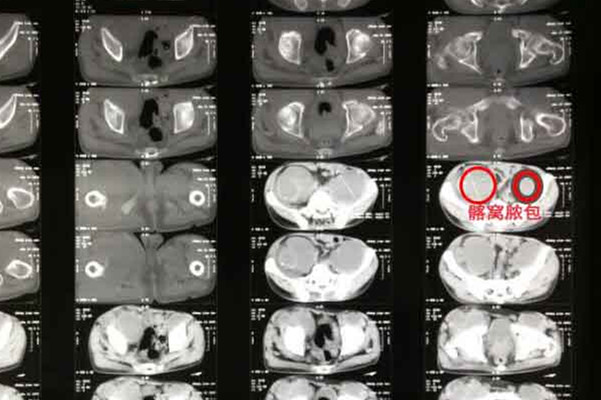

3、在手术治疗过程中,局部病灶可能清理不彻底,局部脓没有排净,局部清创不够彻底;

后者手术治疗,手术方法包括切开排脓、病灶清除(植骨矫形)两种类型。但具体是否需要手术还是需要医生根据患者病情严重程度来看,切勿反复手术,因为会对全身和局部以及对病人体质的消耗和患部的破坏比较大,给骨组织的修复造成很大的障碍。